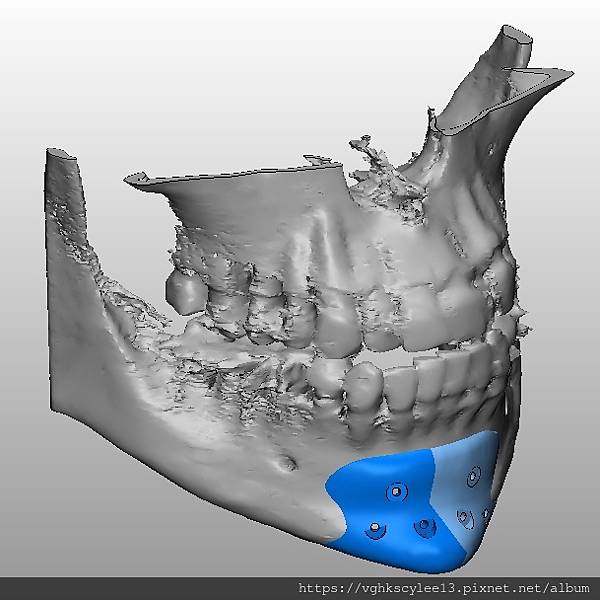

(下圖)3D模擬後工程師版的設計下巴假體的外型。

經過李醫師醫師對客戶外型的判斷,修改工程師的設計,建議更改後的假體模型(下圖)

(上圖)經過李醫師醫師對客戶外型的判斷,修改工程師的設計,建議更改後的假體模型。所以嘍,醫師的美感與專業度必須要做判斷,3D列印只是精準工具但是必須有專業醫師的判斷才可以完美!

下圖: 在李醫師確認後完美精準例印

窄小後縮的下巴,以精準3D列印技術來客製化醫師判斷後的外型下巴假體,一起改善嘴形相對的狀態。

窄小後縮的下巴,以精準3D列印技術來客製化醫師判斷後的外型下巴假體,一起改善嘴形相對的狀態。

3D模擬後 列印出吻合的設計下巴假體